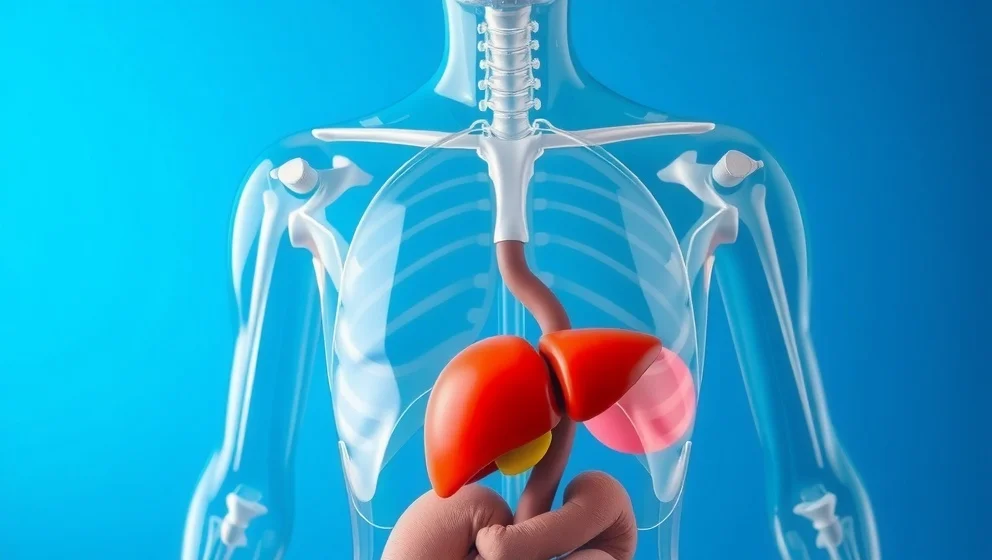

Buken ligger mellan revbenen och bäckenet. Du lär dig var de viktiga organen sitter och hur magen, levern och tarmen fungerar tillsammans.

Gallblåsan sitter gömt under levern på höger sida av magen. Du får veta vad gallblåsan gör och varför den är viktig för matsmältningen.

Levern sitter under höger revben och väger ungefär 1,5 kilo. Den är kroppens största inre organ och gör många viktiga jobb för att hålla dig frisk.